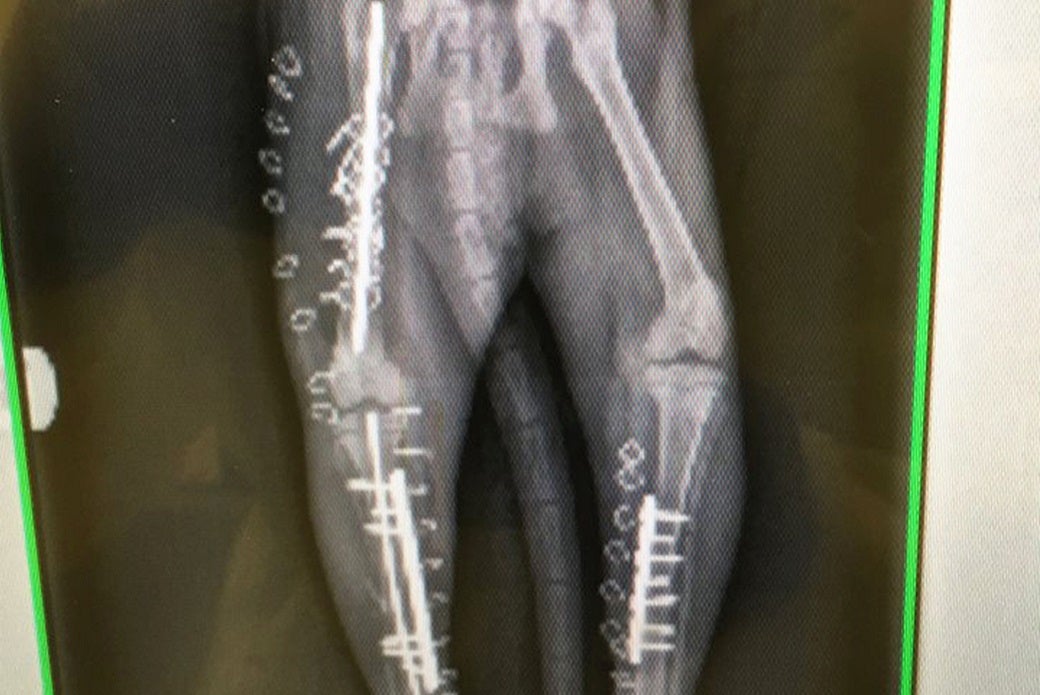

X-rays soon revealed multiple limb trauma, including bi-lateral fractures of the tibia and fibula (the two bones that comprise the lower rear legs), and a fracture of the right femur, or thigh bone.

Working with a team of animal and veterinary technicians including Jennifer Doyle, Anya Hayes, Michaelene Albert, Gregory Moran, Amanda Della Cerra, Norman Salters, and intern Rachel Warnes, as well as a host of recovery, intensive care and radiology technicians and assistants, Dr. Gayle surgically repaired Squeakers’ broken bones with pins, plates, screws and wire.

An X-Ray shows the hardware in Squeakers’ legs after repair.